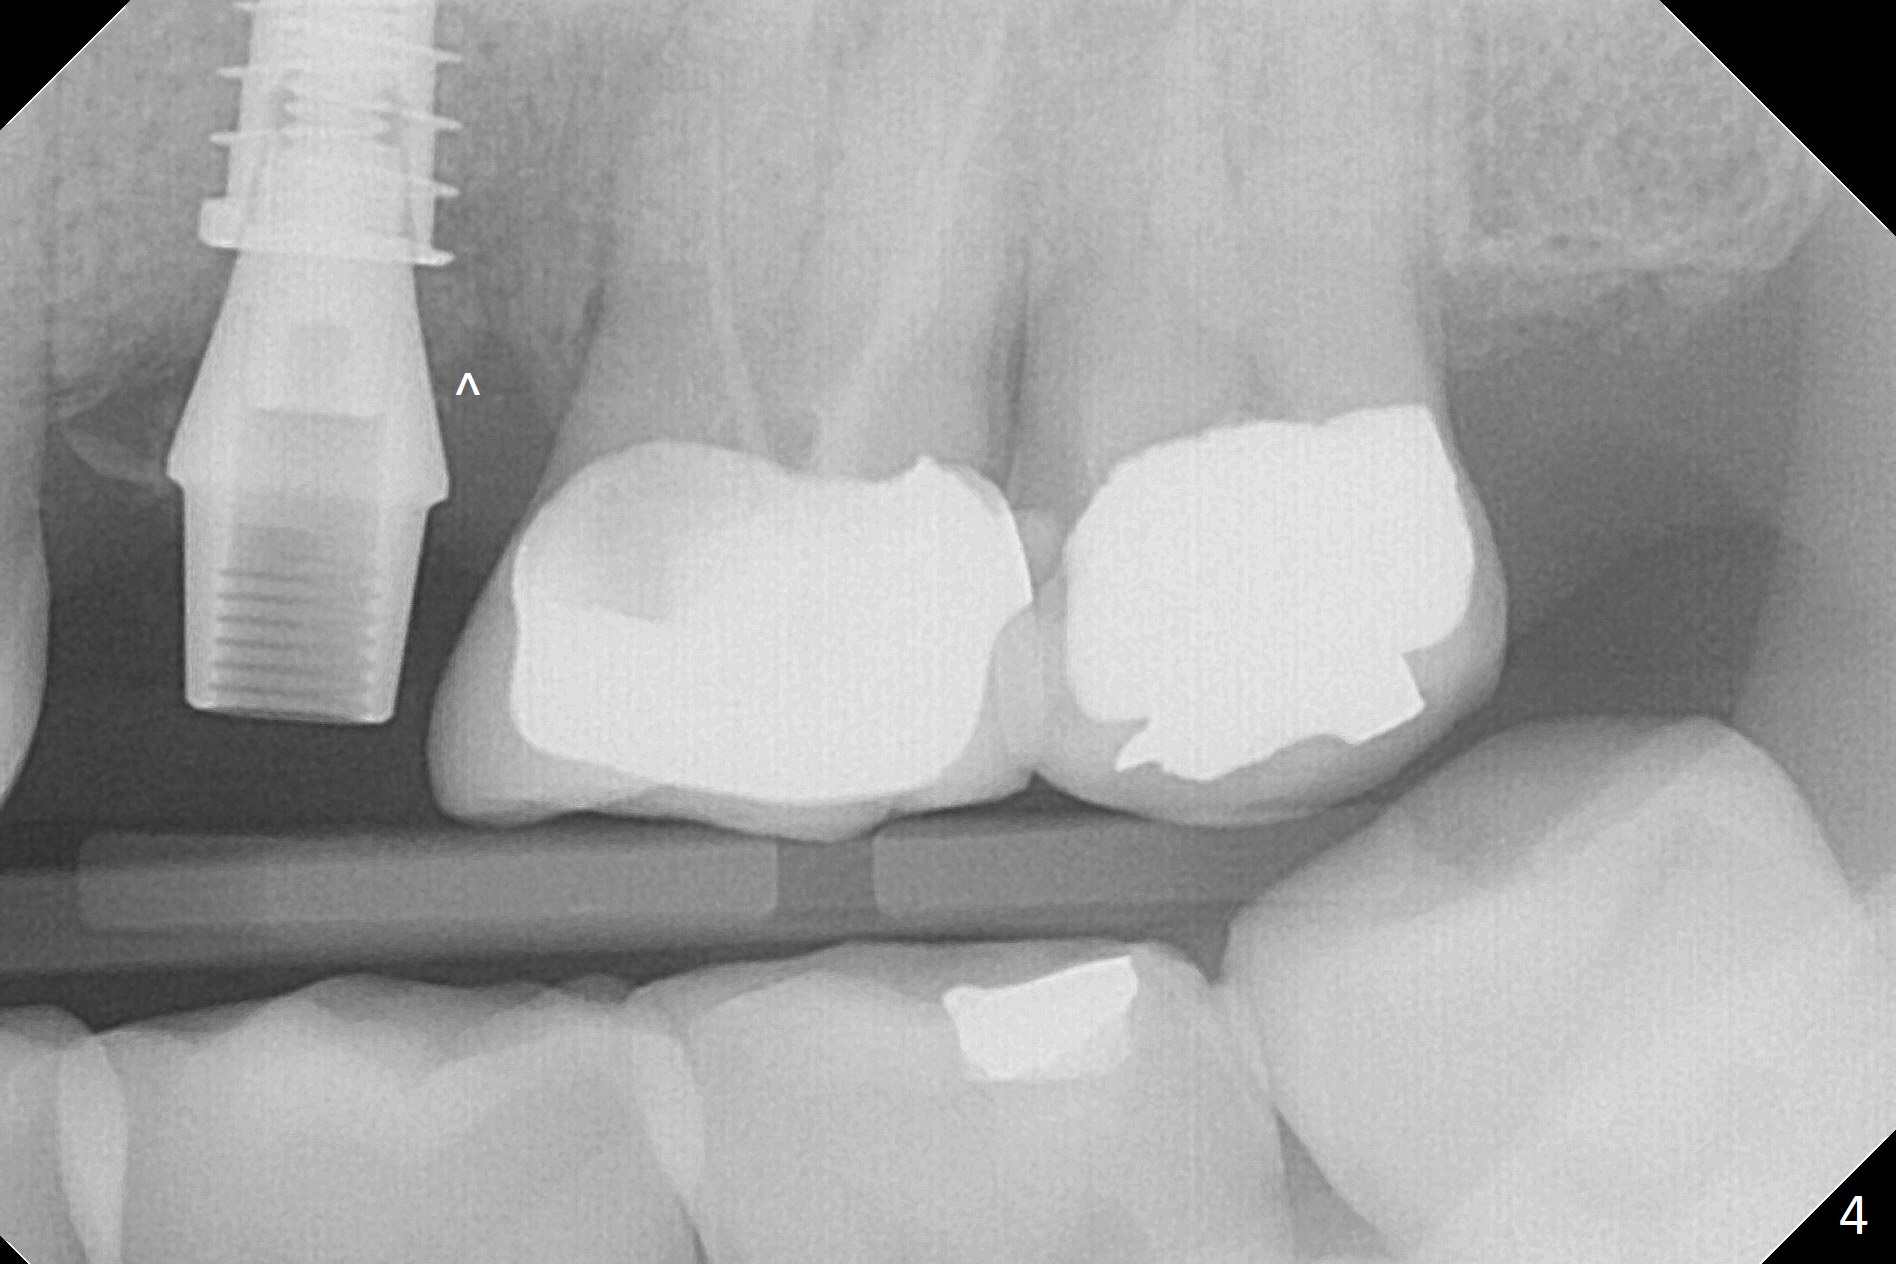

Magic Split is used to start access (flapless) and initial bone expansion at #14. The split does not go deep, since bone density is high in the deep portion. A 1.6 mm drill has to be used for 13 mm (Fig.1). Note the low bone density in the distobuccal socket (*). Later the osteotomy extends to 15 mm (gingival level). After 3.8 mm Magic Drill (MD) for 15 mm, a 4x11 mm dummy implant is placed with insertion torque of 60 Ncm (implant motor, Fig.2). After 4.3 mm MD, a 4.5x11 mm IBS implant is placed with insertion torque of 60 Ncm for implant motor >40 Ncm for torque wrench (Fig.3). The implant seems to be placed deep, but the buccal plate feels to be low. Following bone graft buccally, especially distobuccal (Fig.4,5 ^), a 5x4(3) mm abutment is placed. The buccal gingiva is torn during bone graft (Fig.6 >). Periodontal dressing is applied around the abutment (for increased retention) for wound protection.